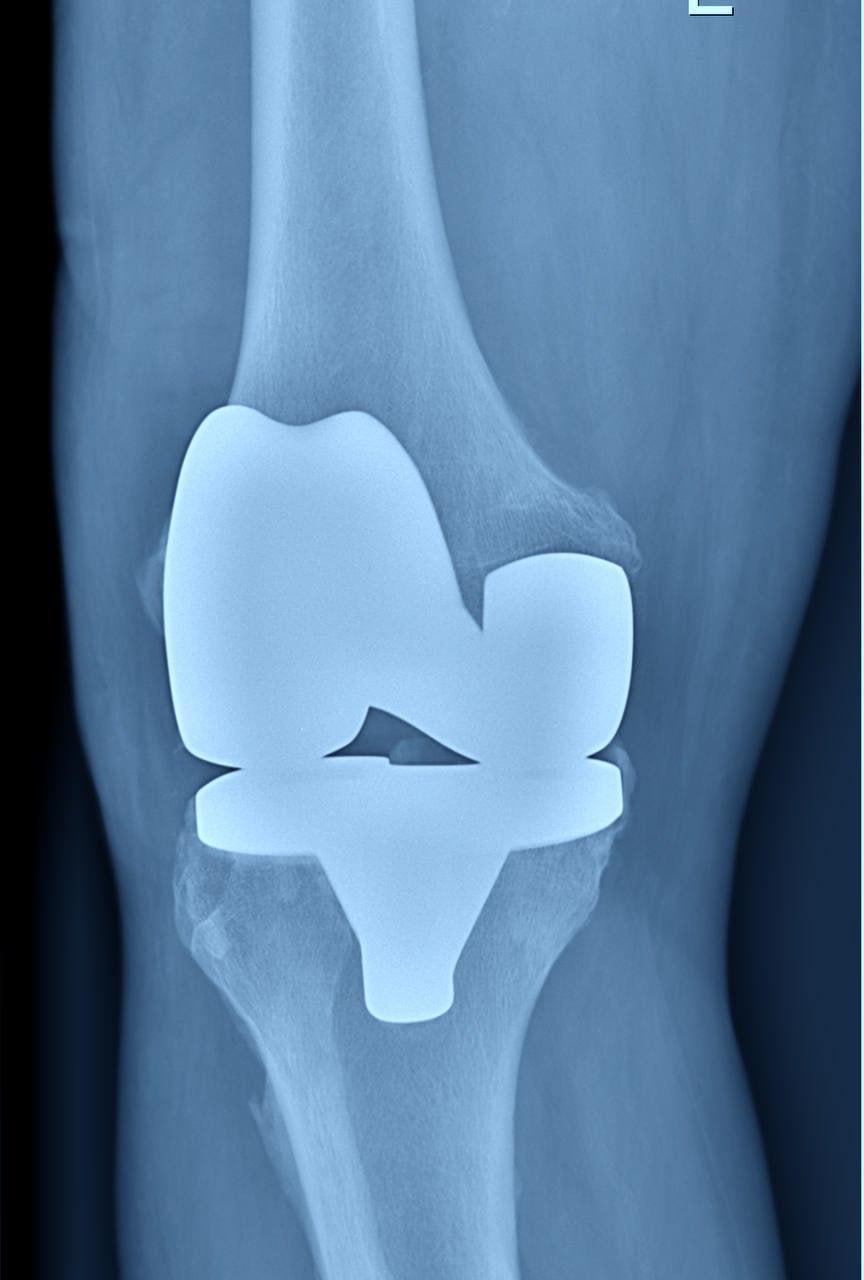

В Балахнинской ЦРБ начали выполнять операции по замене коленных суставов

На счету балахнинских врачей уже пять таких операций для людей с разрушенными коленными суставами.

Чаще всего артроз развивается из-за лишнего веса, перенесённых вирусных инфекций, сверхнагрузок, влияет и наследственность. После замены сустава исчезает боль, восстанавливается объём движений в суставе и способность опираться на ногу.

В больнице пациенты проводят не более недели, реабилитация после замены суставов занимает около 3-4 месяцев. Операции проводятся бесплатно, по полису ОМС, сообщает главный редактор ИА "Стационар-пресс" Алексей Никонов.